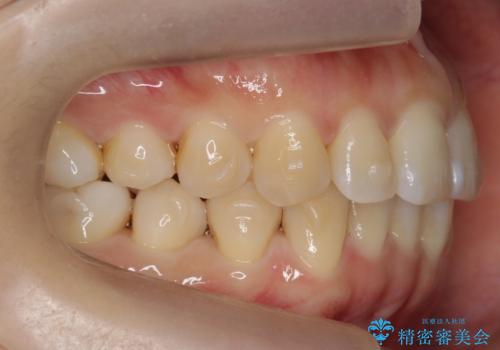

下の前歯のがたつき インビザラインで

- 前歯のがたつきを主訴に来院。

インビザラインで上下の前歯をわずかに削って並べました。

下の歯の叢生を並べると多少ブラックトライアングルがでることがあります。